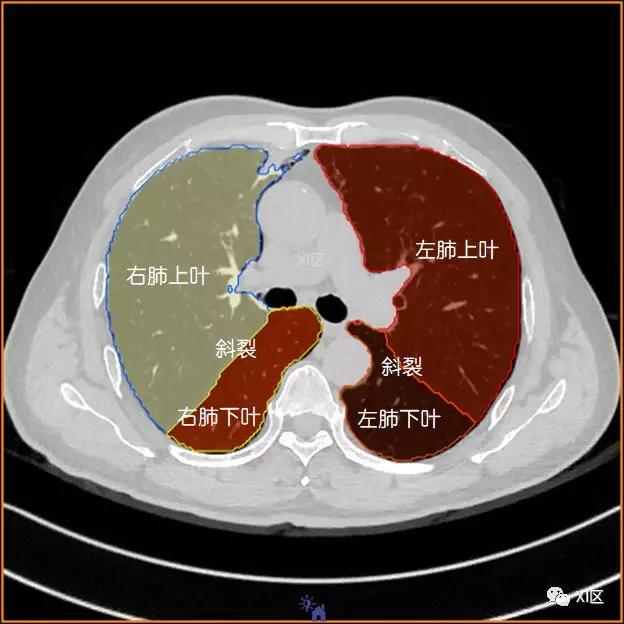

横断位

左肺借斜裂成上、下两叶;右肺借斜裂和水平裂成上、中和下叶三叶。

在进行肺的分段时,可以上下观察浏览,沿着相应气管的走形可以更容易准确地进行分段。